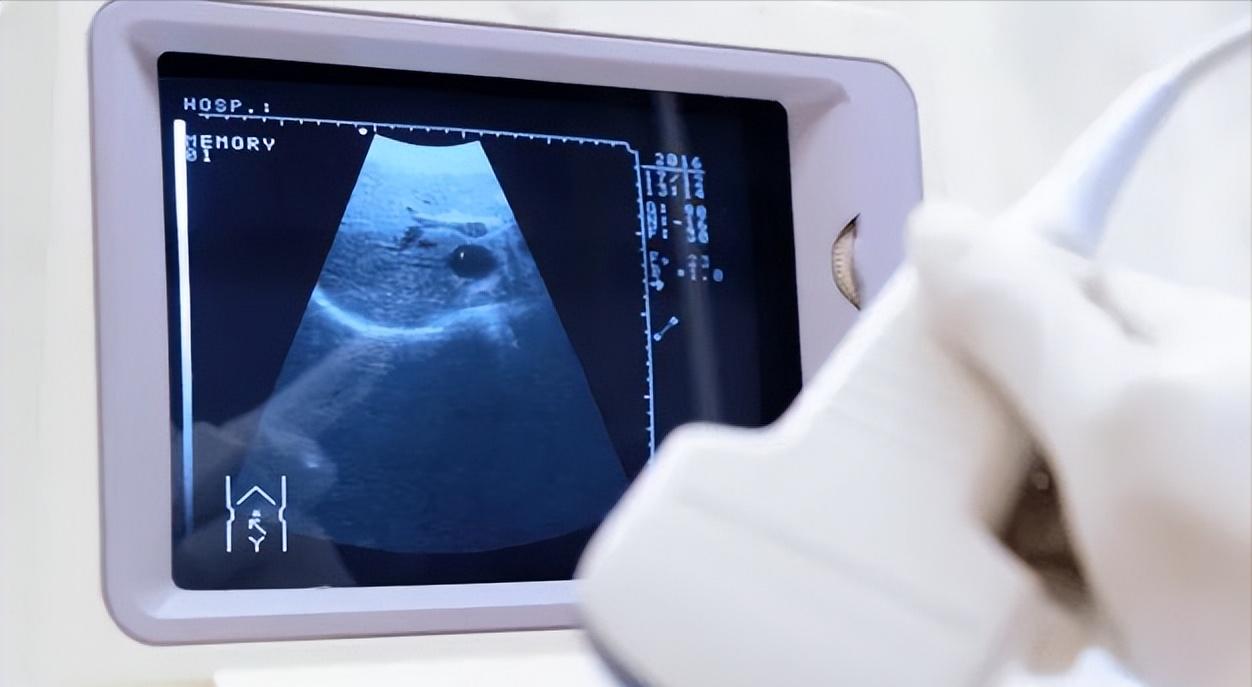

肝脏B超其实就是腹部超声检查,通过声波反射来观察肝脏的形态、大小、回声等特征,从而发现是否存在病变。

它并不涉及辐射,对身体无创伤、无痛苦,属于非常安全的检查方式。

检查虽简单,6点细节要牢记虽然B超操作简单,但若检查不规范,也可能影响结果准确性。以下6点,是很多人常常忽略却非常关键的检查细节。

1. 检查前禁食6小时

进食后胆囊收缩,肠道充气增加,容易干扰肝区声像图,导致结果不清晰。建议检查前禁食4~6小时为宜。

4. 体型影响成像效果

肥胖、腹壁较厚或肠气多时,B超探头难以穿透,成像清晰度下降。医生可能会建议采取不同体位,或必要时转为CT检查。

B超无法直接显示肝功能,也不能检测肝炎病毒、肝酶水平,不能替代抽血检查。它是结构性检查,不能反映功能性问题。